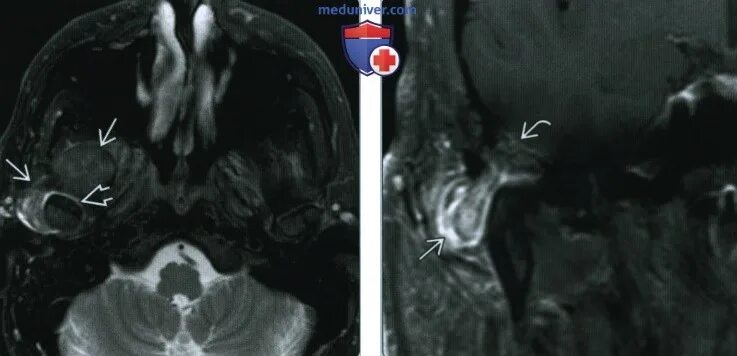

Т2 гипоинтенсивный